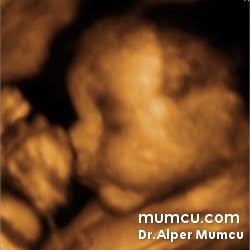

3 Boyutlu ultrason resimleri

Bu sayfadaki fotoğraflar degişik zamanlarda ve farklı hastalarda Dr. Alper Mumcu tarafından çekilmiştir.

11 haftalık gebelik